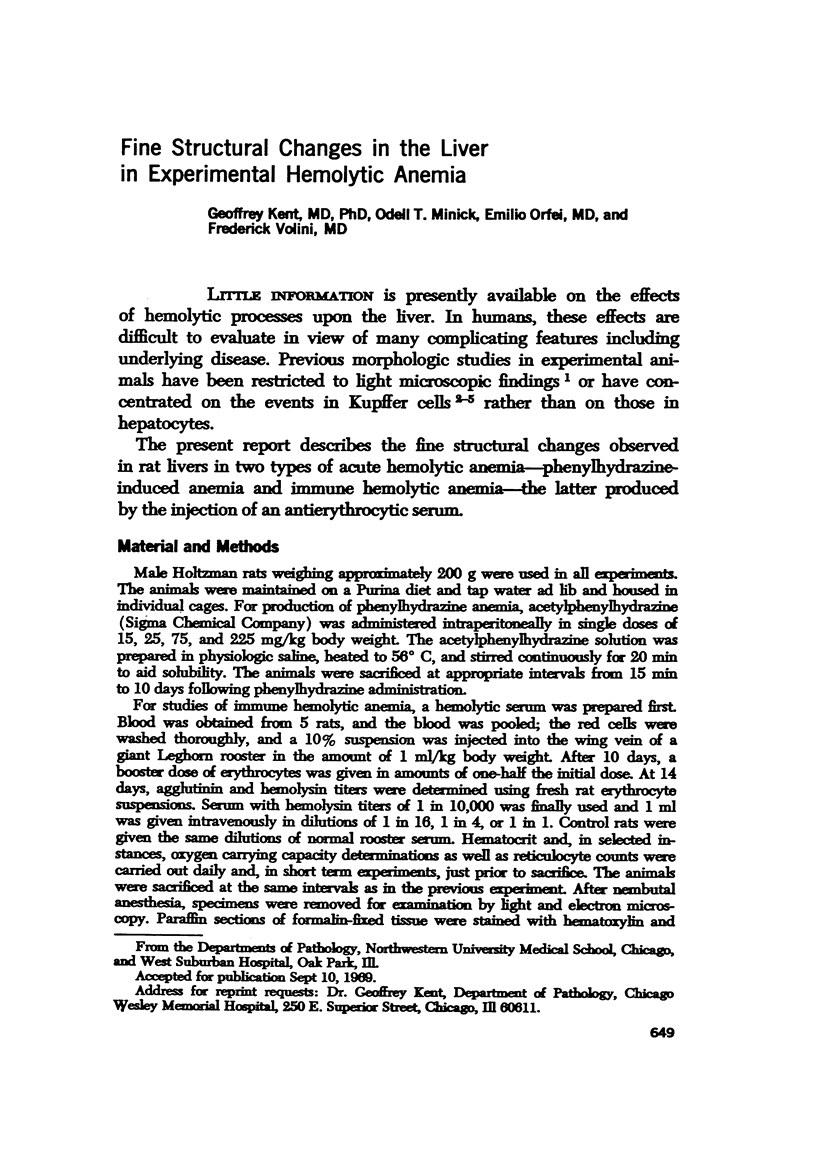

Full text